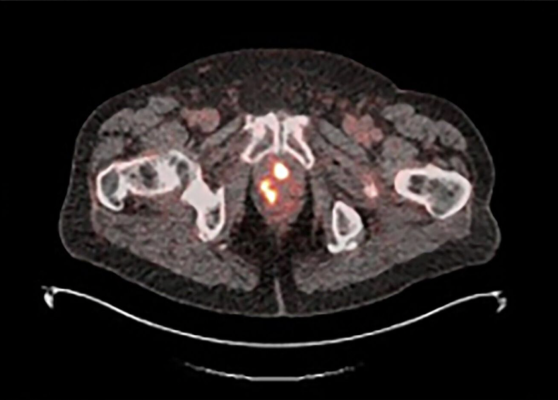

18F-rhPSMA-7.3 PET image showing multiple areas of uptake in the prostate gland in a man with newly diagnosed prostate cancer Photo courtesy of Blue Earth Diagnostics

The findings presented at SUO reported on the first results of the Phase 3 LIGHTHOUSE trial on the diagnostic performance and safety of 18F-rhPSMA-7.3 in men with newly diagnosed prostate cancer planned to undergo radical prostatectomy (RP). Co-primary endpoints were patient-level sensitivity and specificity of 18F-rhPSMA-7.3 PET for the detection of pelvic lymph node (PLN) metastases using histopathology as the standard of truth. The endpoints were evaluated for the Efficacy Analysis Population (EAP) of 296 patients who underwent 18F-rhPSMA-7.3 PET and had subsequent RP and PLN dissection. Based on the majority read from the three blinded, independent PET readers, the overall specificity of 18F-rhPSMA-7.3 PET/CT in the LIGHTHOUSE study was 96% (217/226). By majority read, the specificity was 95% (139/146) for high-risk or very high-risk, and 98% (78/80) for unfavorable intermediate-risk patients. The overall sensitivity of 18F-rhPSMA-7.3 PET/CT in the LIGHTHOUSE study was 24% (17/70) by majority read, which is consistent with reports to date of sensitivity within the class of PSMA-targeted diagnostic imaging radiopharmaceuticals. By majority read, the sensitivity was 27% (14/51) for high-risk or very high-risk, and 16% (3/19) for unfavorable intermediate-risk patients. No serious adverse events were observed in the LIGHTHOUSE study. Overall, 28 of the 356 (7.9%) patients in the Safety Population had at least one treatment-emergent adverse event that was considered possibly related to 18F-rhPSMA-7.3. The most frequently reported adverse event for patients in the Phase 3 LIGHTHOUSE study was injection site pain among 0.8% (3/356) of patients.